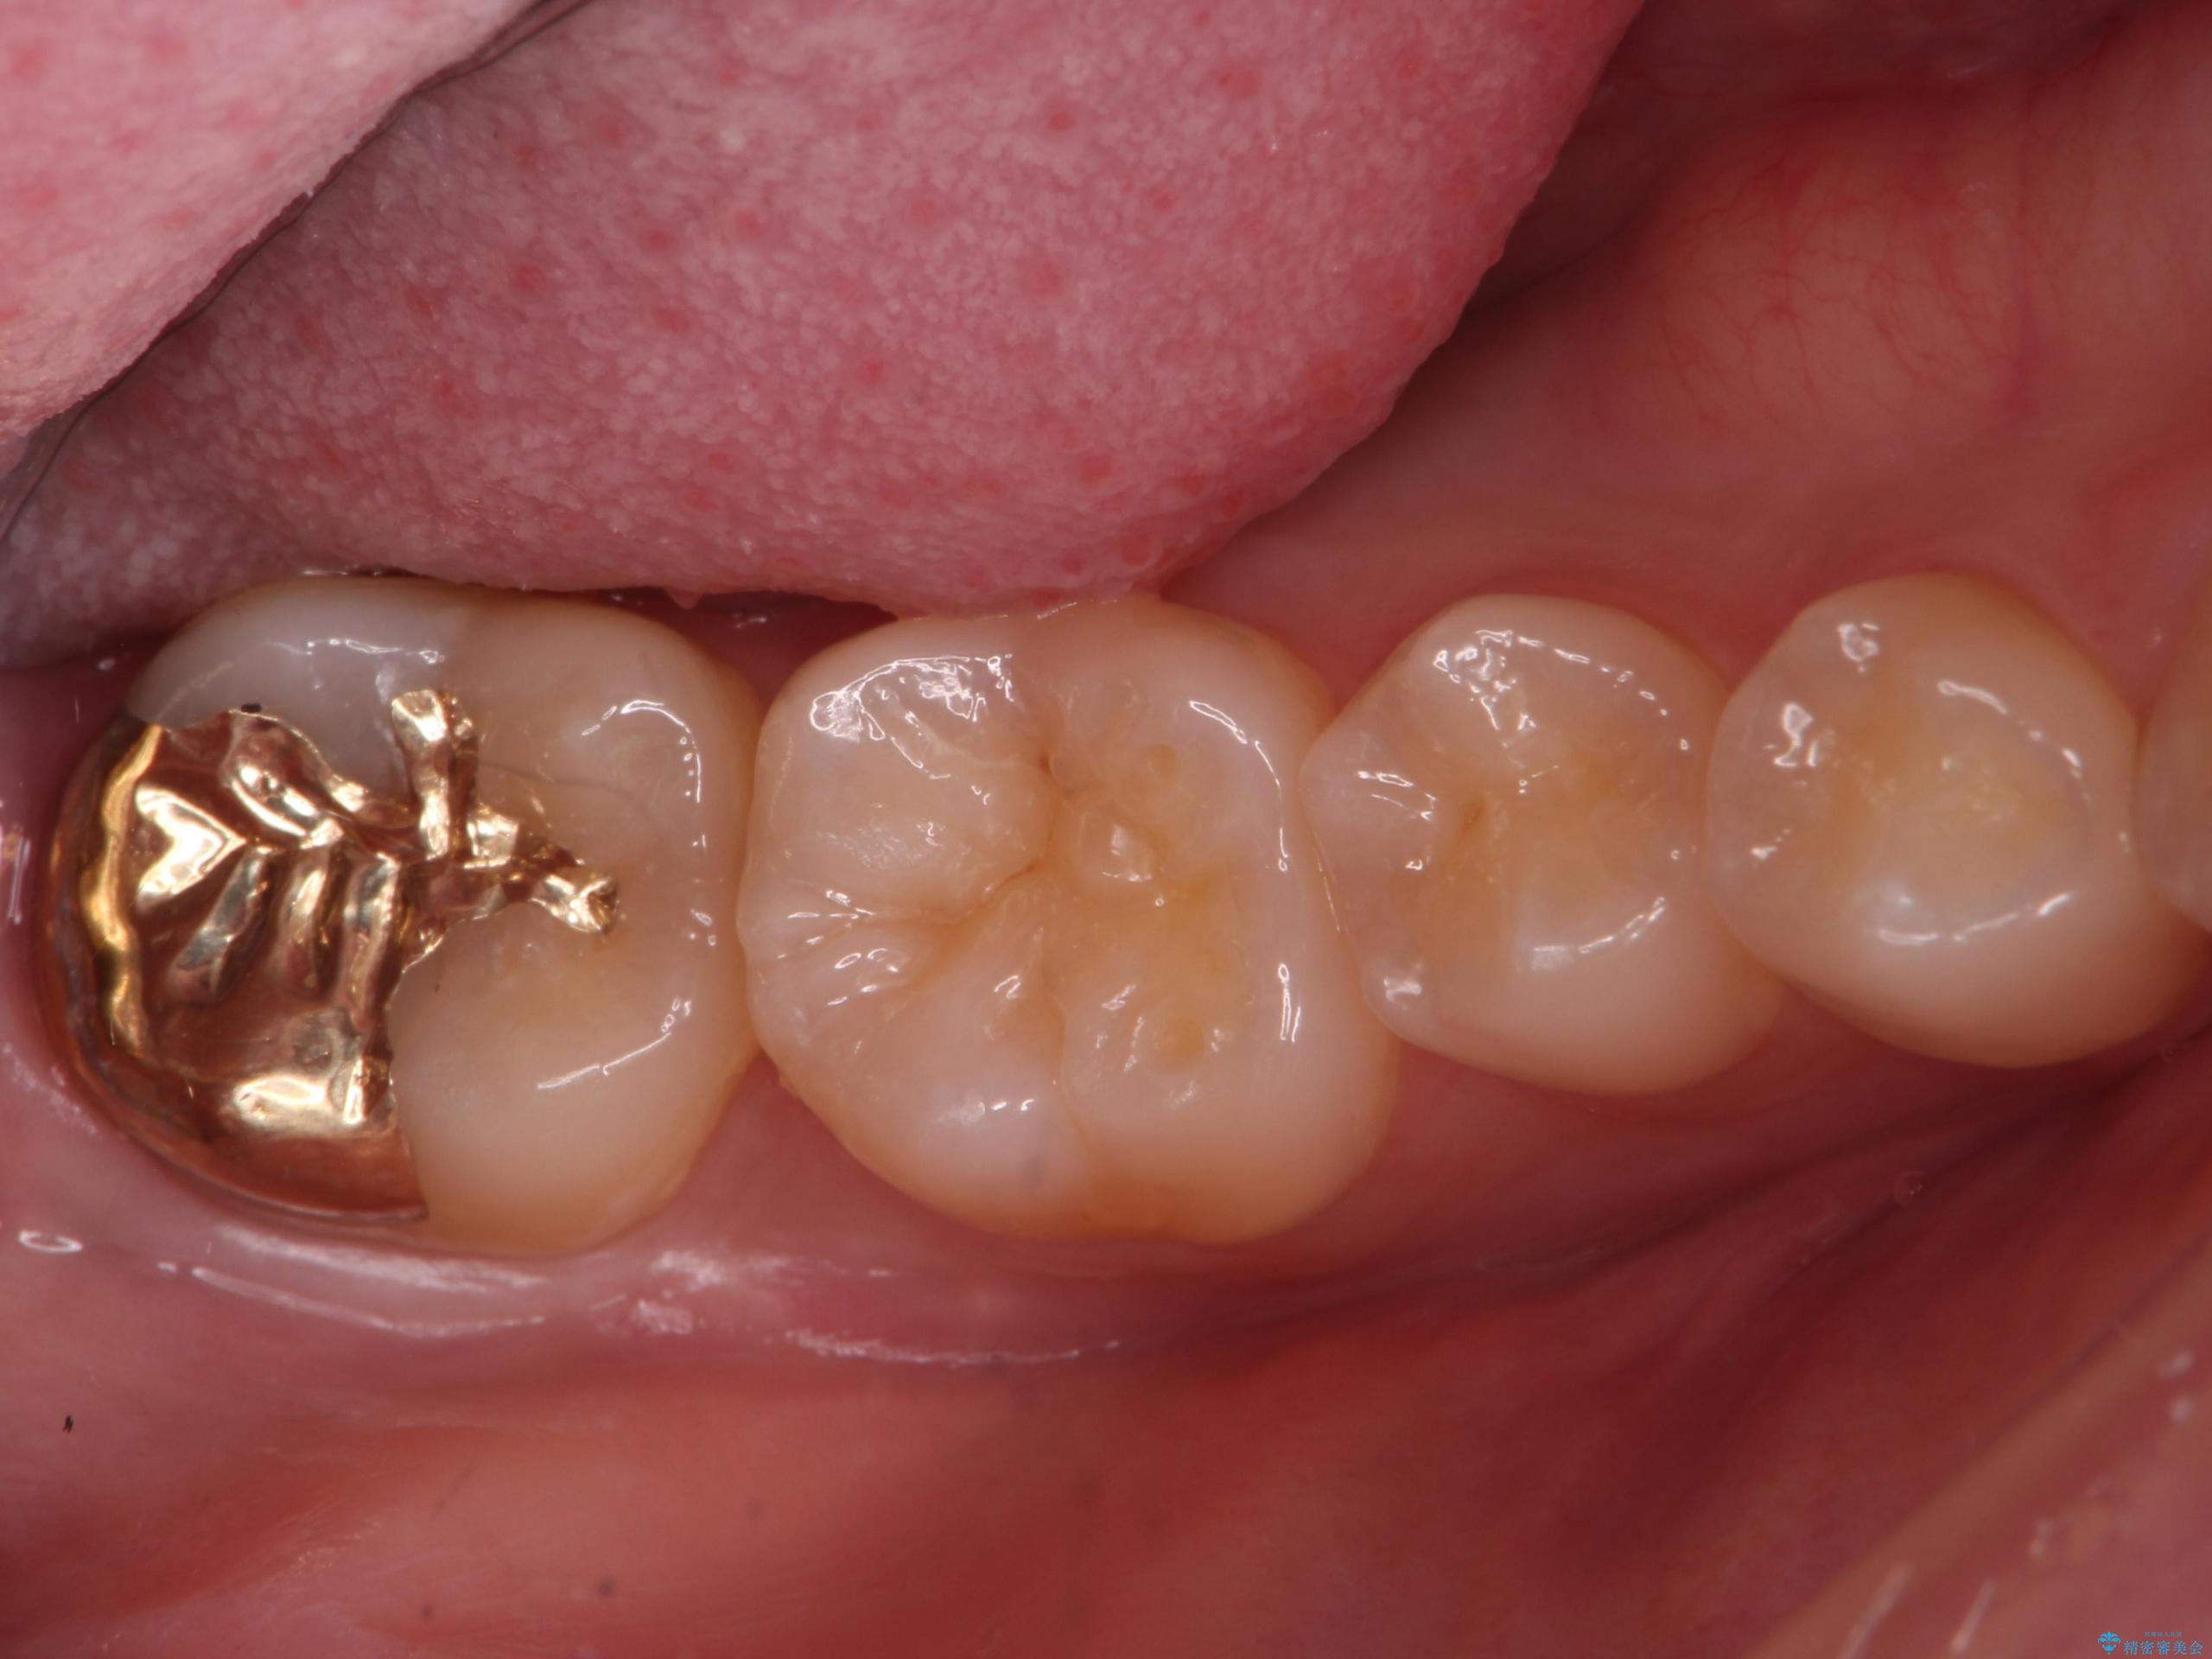

虫歯治療後、精度の良いゴールドアンレーへ

比較的大きな虫歯でしたがゴールドでの修復にすることで歯の削る量を抑え、精度の高い治療を行うことができました。

親知らずの問題も同時に解決することで今後の虫歯リスクを抑えています。